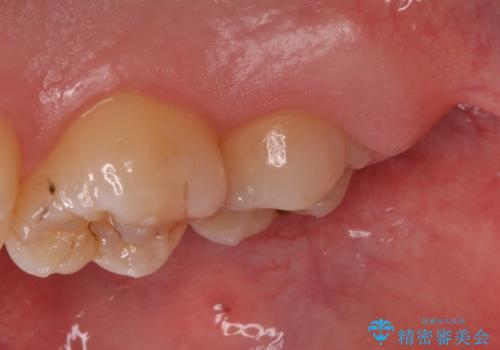

[ 歯肉縁下齲蝕 ] 歯周外科を行った虫歯治療

![[ 歯肉縁下齲蝕 ] 歯周外科を行った虫歯治療の症例 治療前](https://seimitsushinbi.jp/wp/wp-content/uploads/2023/05/a64b0434e936f69092c4868d7fec9b97-500x350.jpg?v=1684994566)

![[ 歯肉縁下齲蝕 ] 歯周外科を行った虫歯治療の症例 治療後](https://seimitsushinbi.jp/wp/wp-content/uploads/2023/05/fa1958073cf4724216bea0bd1890c46a-500x350.jpg?v=1684994581)